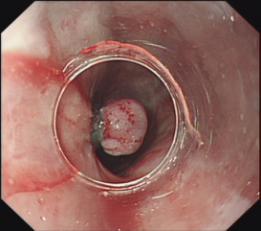

6. 消化道早癌內(nèi)鏡下黏膜切除術(shù)(EMR)、內(nèi)鏡黏膜下剝離術(shù)(ESD)、內(nèi)鏡下多環(huán)套扎粘膜切除術(shù)(MBM),消化道粘膜下腫瘤內(nèi)鏡下挖除術(shù)(ESE)、內(nèi)鏡下全層切除術(shù)(EFR)、內(nèi)鏡下隧道切除術(shù)(STER)及雙鏡聯(lián)合切除術(shù);

結(jié)腸腺瘤粘膜剝離術(shù)